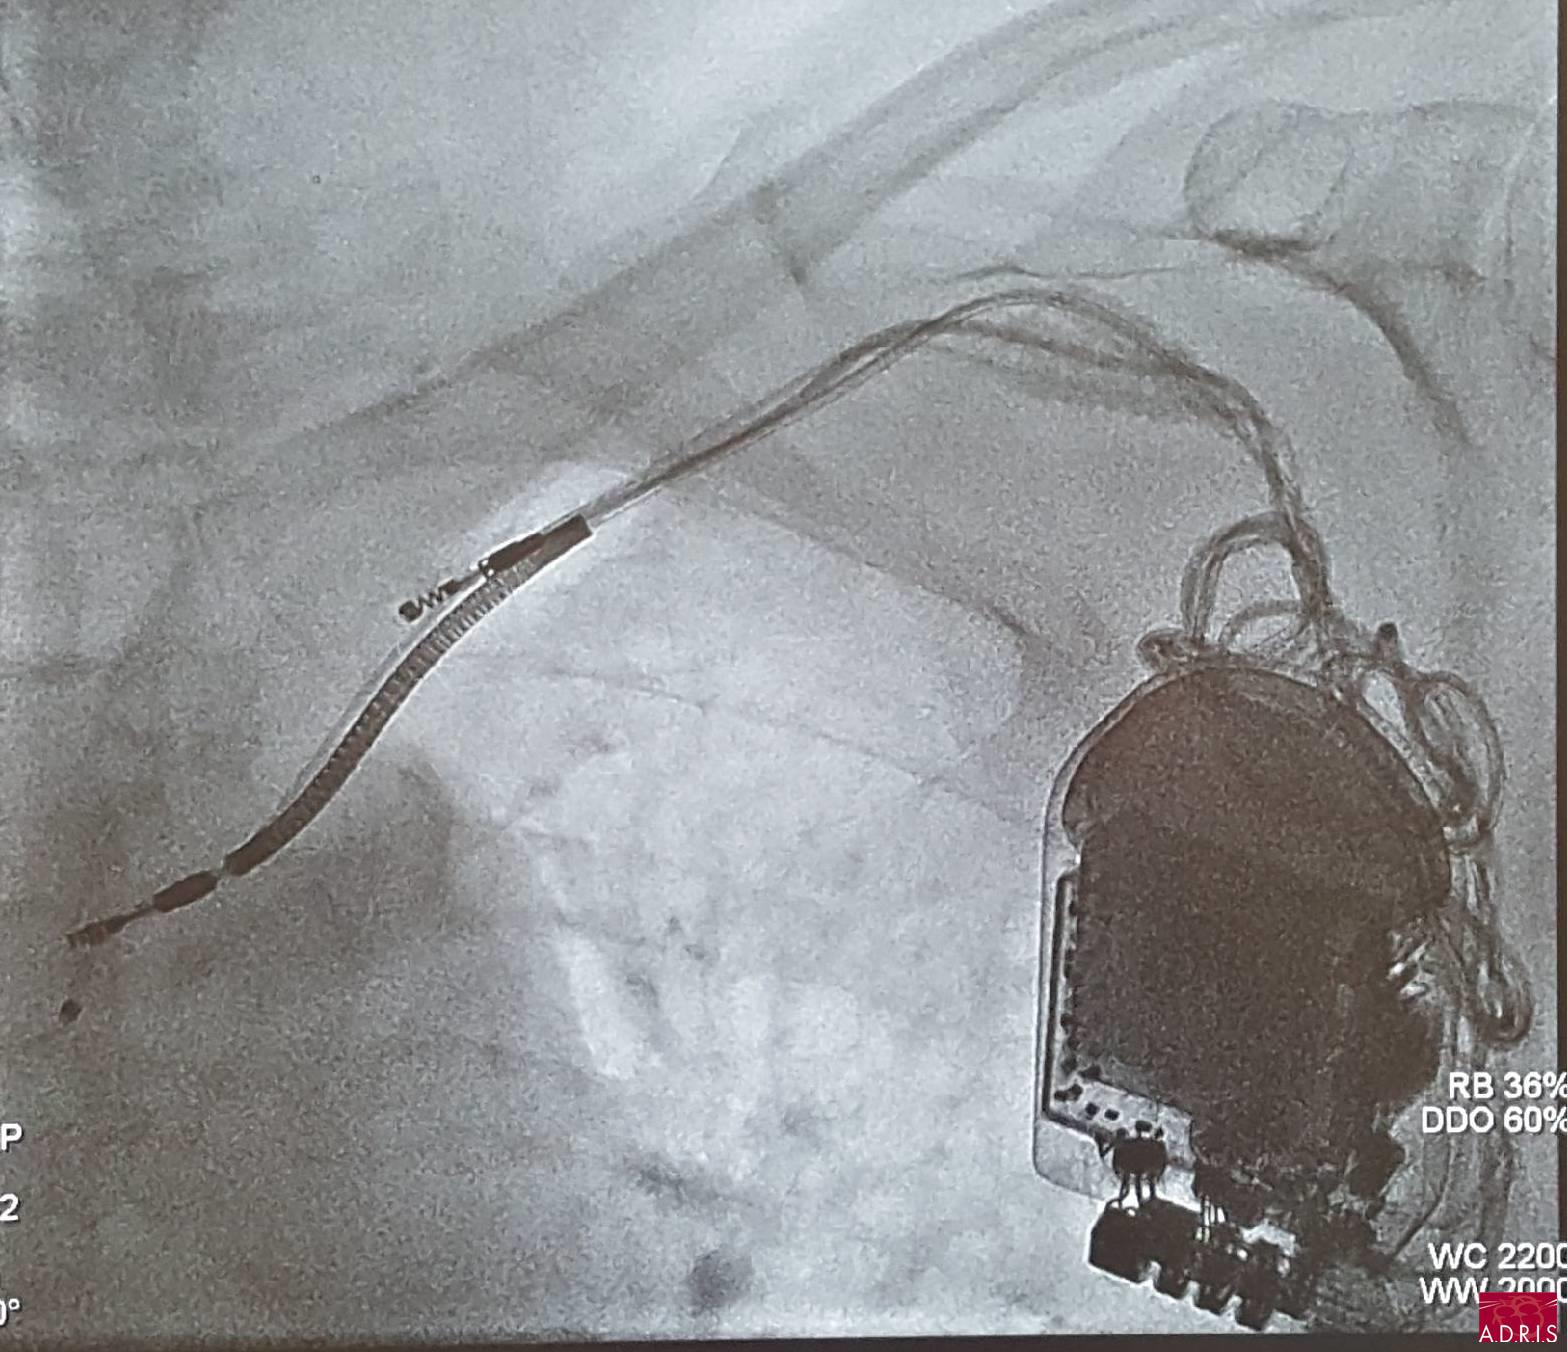

Cas clinique 2

Homme 57 ans mobilisation du boîtier de défibrillation, déplacement des 3 sondes.